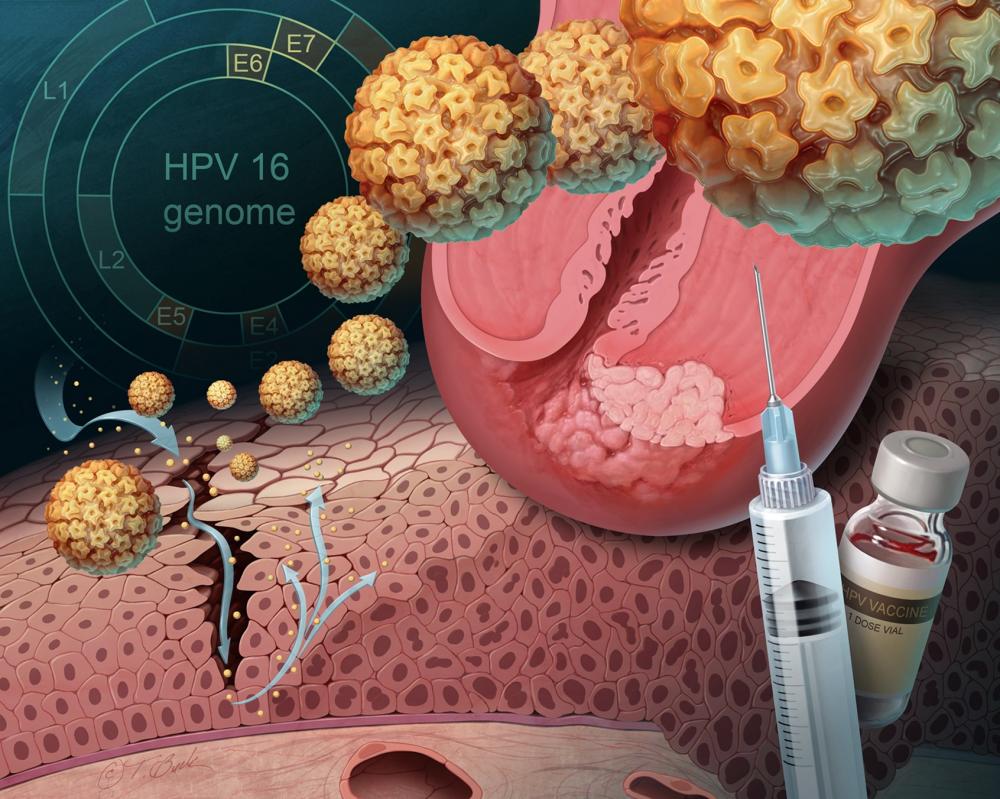

Факторы Риска ВПЧ: Визуальный Обзор и Информация